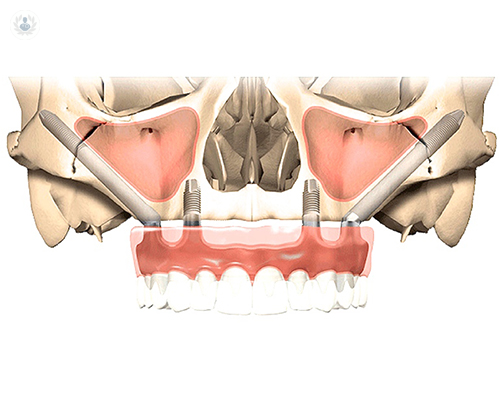

Los implantes cigomáticos son una muy buena alternativa para la rehabilitación implanto-soportada sin injertos en pacientes con maxilares reabsorbidos o con previa pérdida de implantes. Se trata de un procedimiento predecible y con un índice bajo de complicaciones.